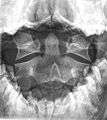

Type 2 dens fracture